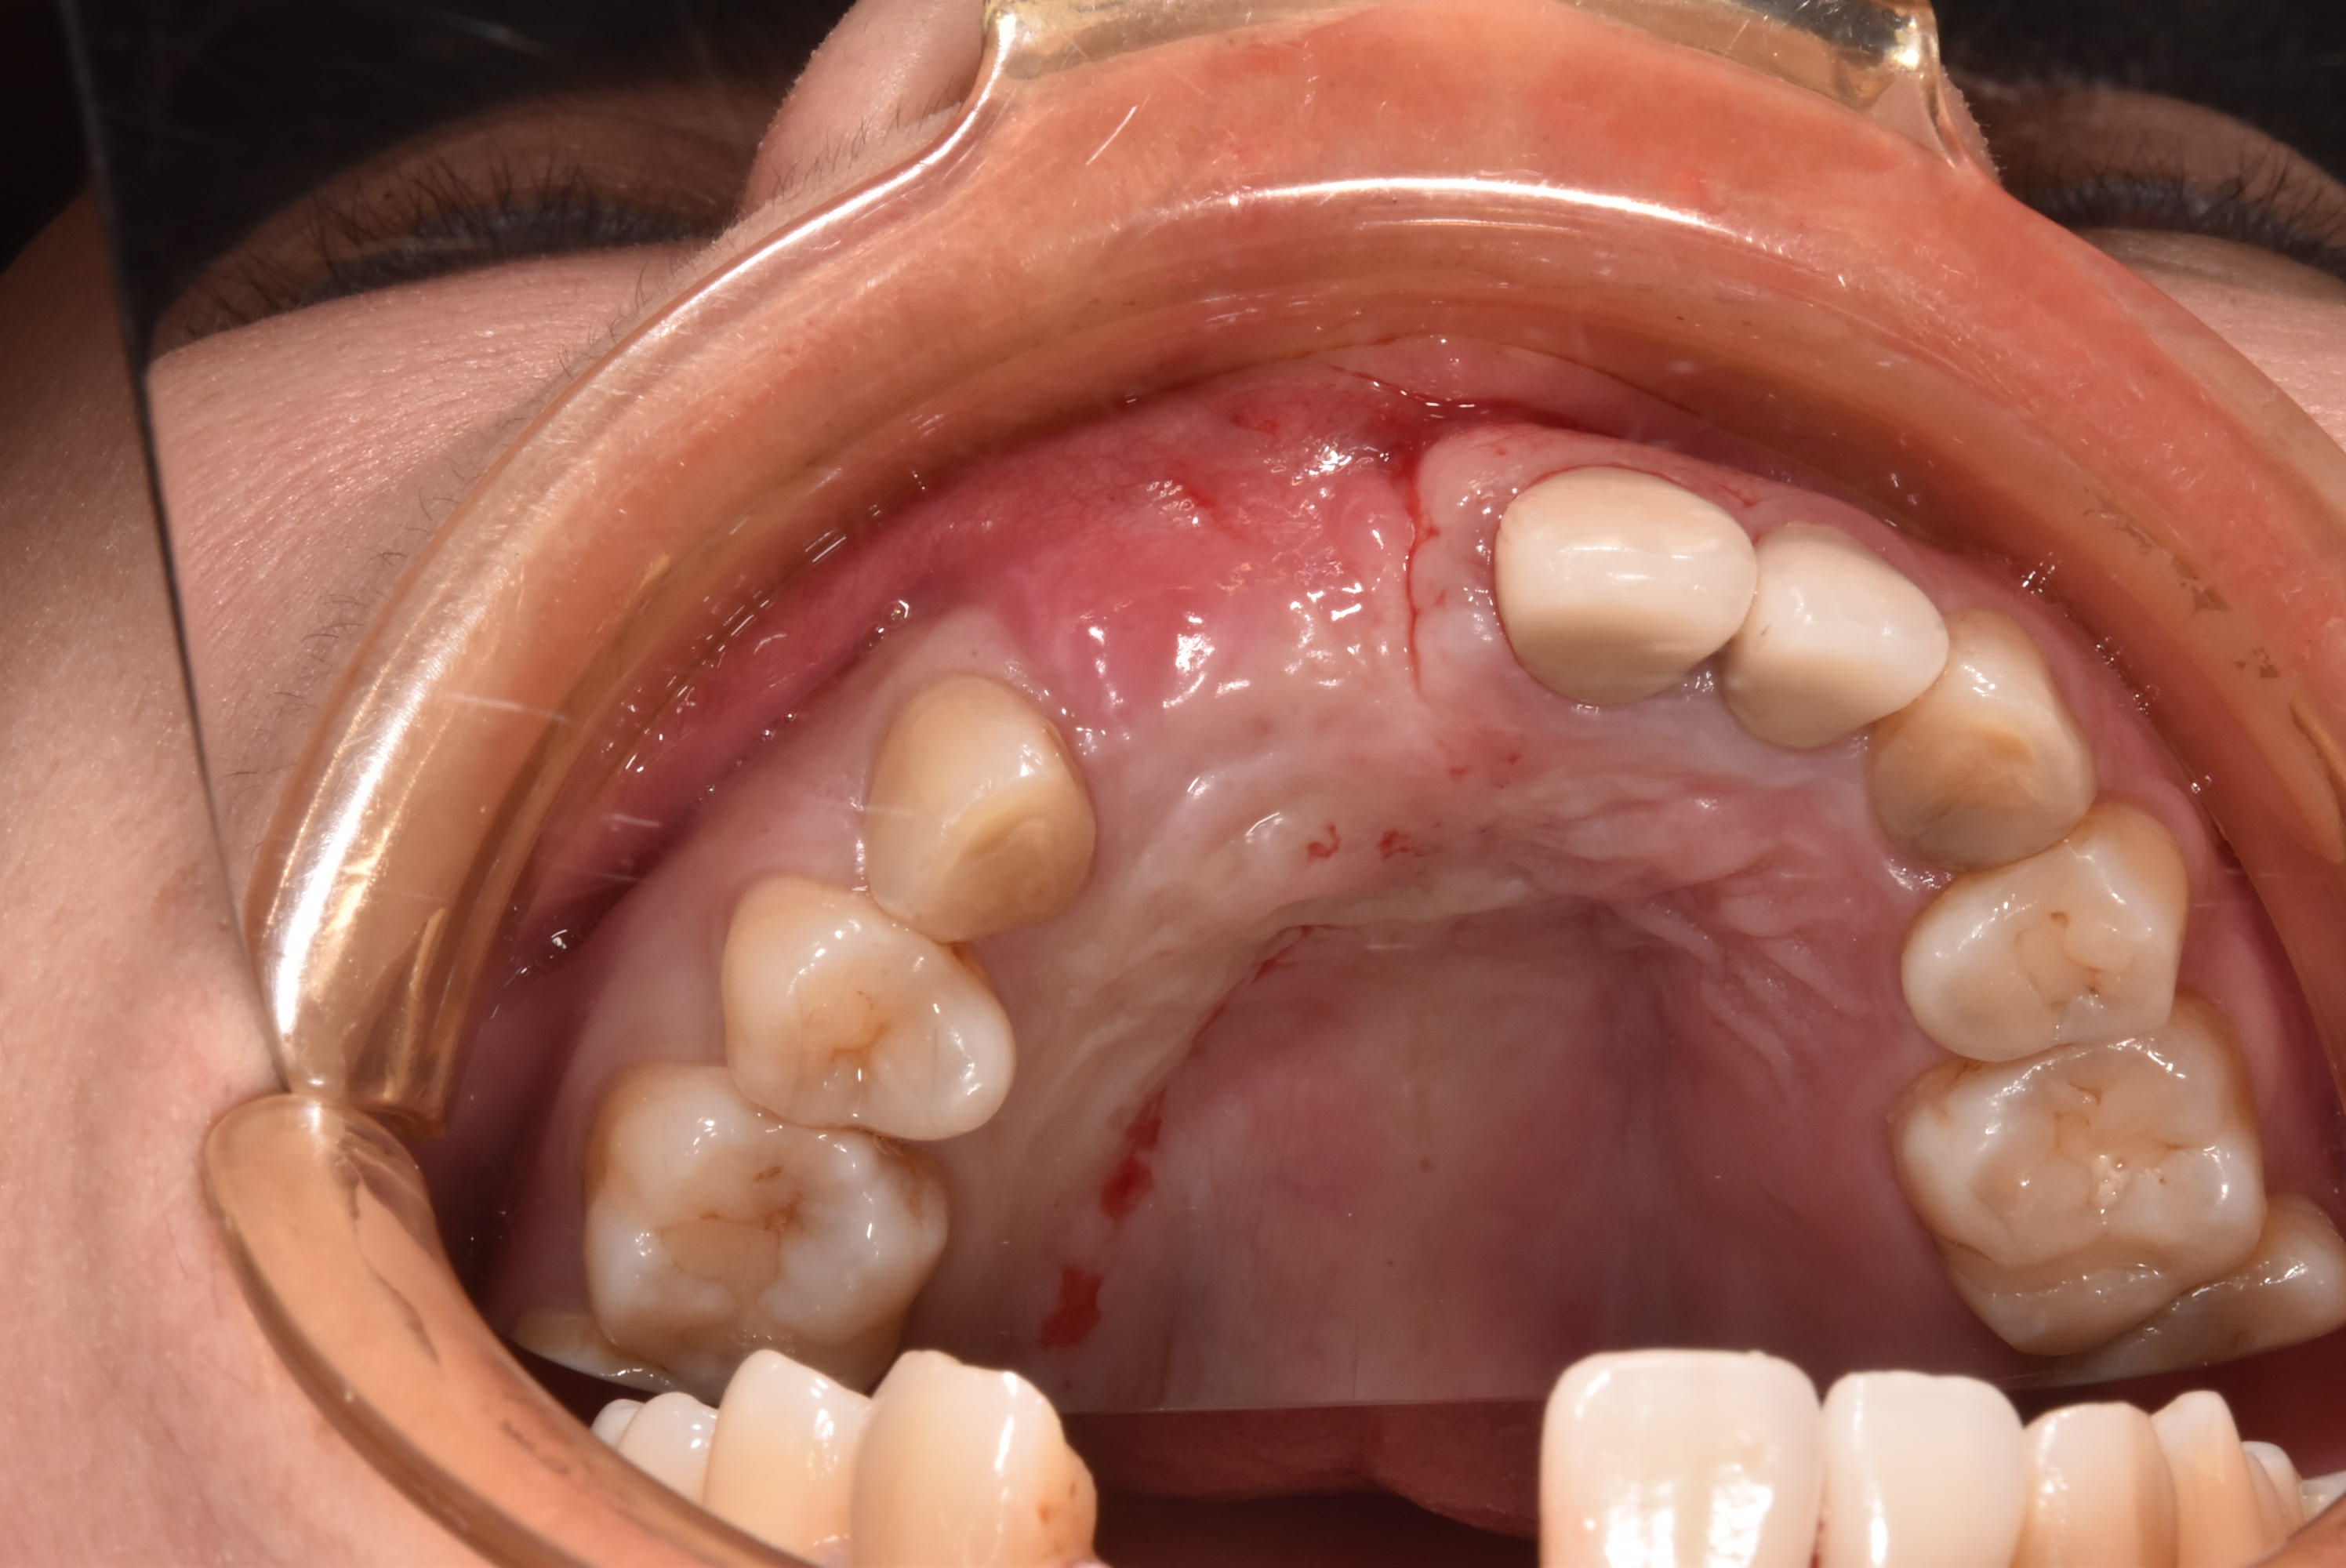

牙齦移植術(補肉)

術前加術後案例

案例三